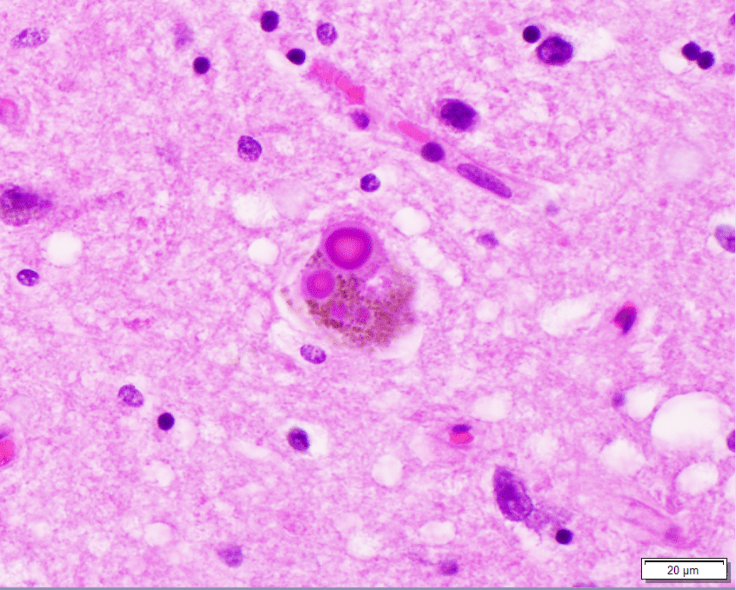

Parkinson’s Disease is a neurodegenerative disease associated with the presence of abnormal pink-purple inclusions, called Lewy bodies, which contain alpha-synuclein protein and are commonly found in pigmented neurons (shown here).